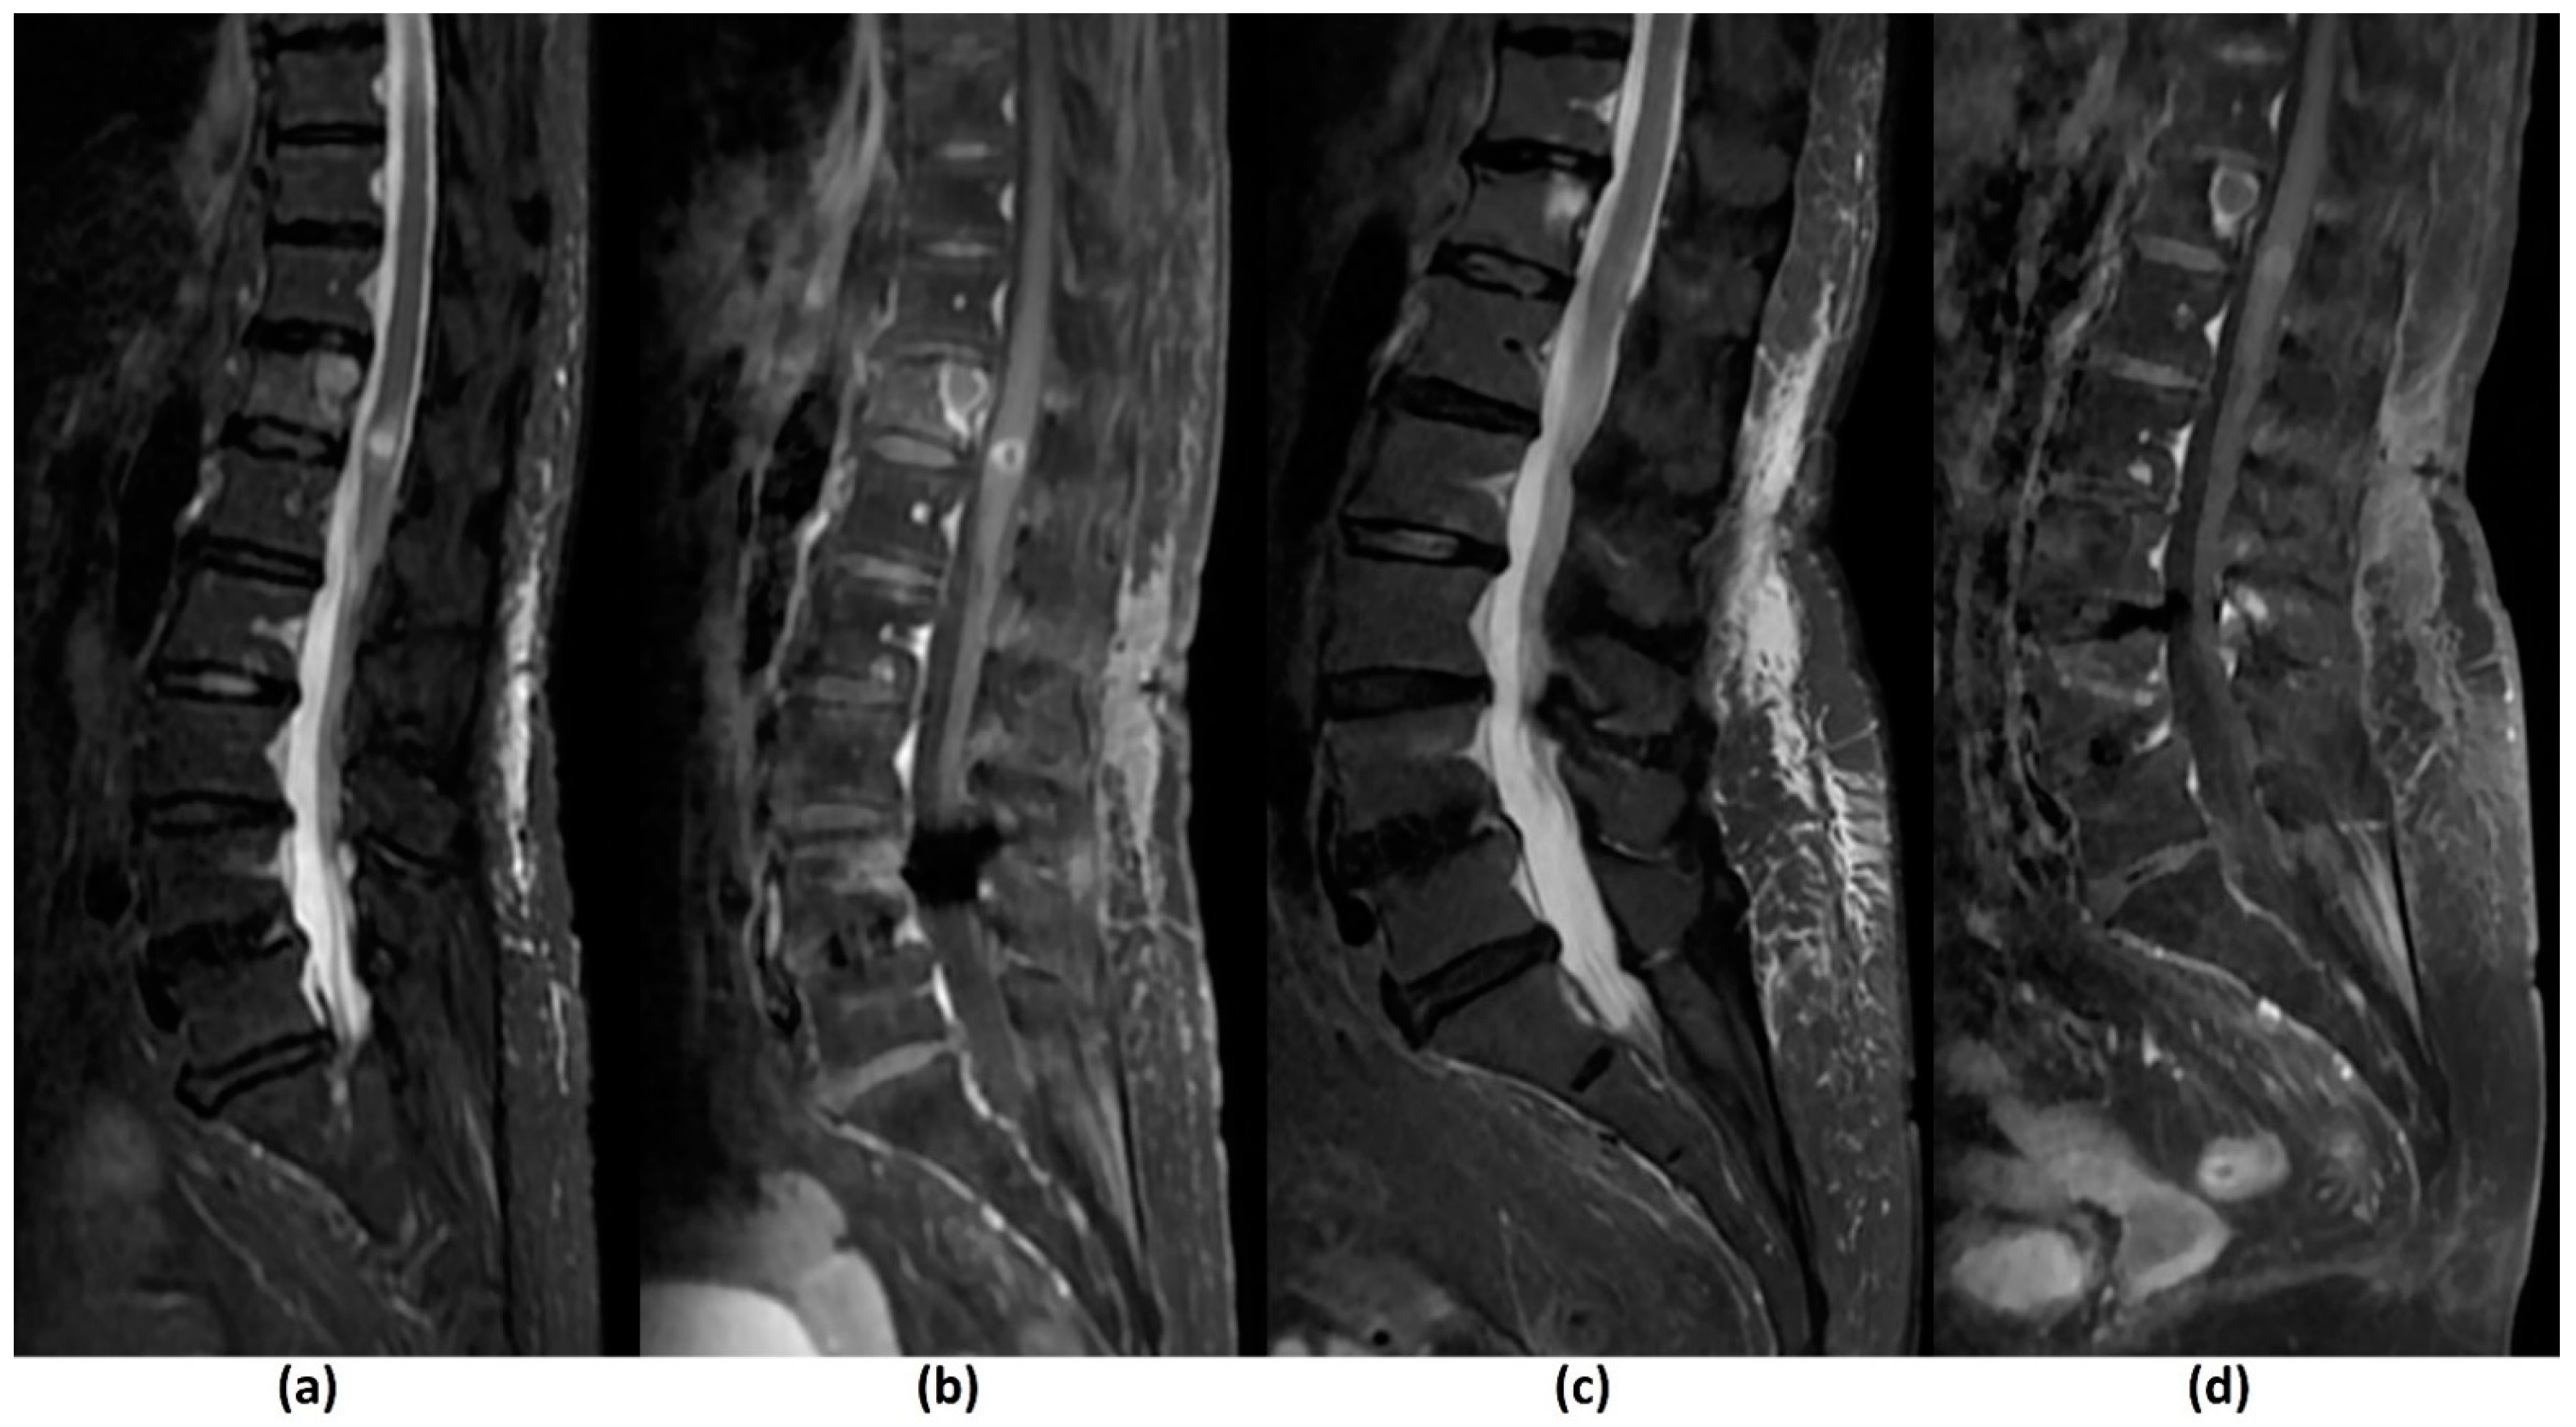

4.3. Post-Treatment Follow-Up

- Hwang, Y.J.; Sohn, M.J.; Lee, B.H.; Kim, S.Y.; Seo, J.W.; Han, Y.H.; Lee, J.Y.; Cha, S.J.; Kim, Y.H. Radiosurgery for metastatic spinal tumors: Follow-up MR findings. AJNR Am. J. Neuroradiol. 2012, 33, 382–387. [Google Scholar] [CrossRef]

- Zhou, J.; Jawad, M.S.; Harb, J.G.; Yee, S.; Yan, D.; Grills, I.S. Quantifying Follow-up T2-weighted MR Image in Local Failure Spinal Tumors after Stereotactic Body Radiation Therapy (SBRT). Int. J. Radiat. Oncol. Biol. Phys. 2014, 90, s6. [Google Scholar] [CrossRef]